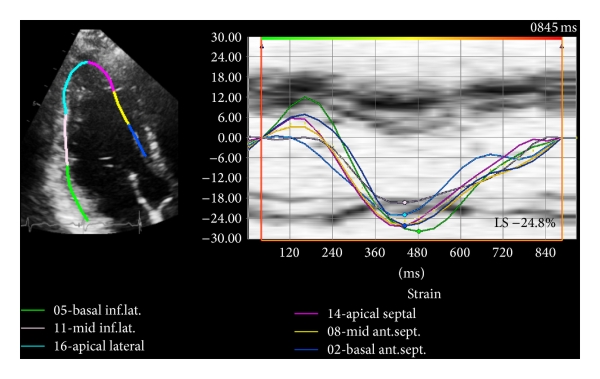

Myocardial peak systolic longitudinal strain was measured offline for both the LV and RV based on the ASE recommendations [21] using commercially available software (Vector Velocity Imaging (VVI) 3.0, Siemens Medical Solutions, Mountain View, CA) using the speckle tracking technique. Briefly, apical 4-, 3-, and 2-chamber images of the LV and an apical 4-chamber view of the RV in DICOM format were obtained for each patient and loaded into the VVI software. Endocardial contours were drawn along the LV and RV border separately for measurement of respective longitudinal strain values (Figures 1 and 2). The contours were adjusted as needed to ensure adequate visual tracking of the endocardium. Any segments that were not tracked adequately after 5 attempts at adjustment were excluded from the analysis. LV peak systolic global longitudinal endocardial strain (GLS) was measured by taking the average of the peak endocardial strain curves in the apical 4-, 3-, and 2-chamber views (16-segment model) (Figure 1). As conventionally done, RV peak systolic global longitudinal endocardial strain (RVGLS) was measured from all 6 RV myocardial segments from an apical 4-chamber view (3 segments of the free wall and 3 segments of the interventricular septum) while the RV free wall peak systolic longitudinal strain (RVFWLS) was obtained from the 3 RV free wall segments only (Figure 2). This distinction is made since measurement of RVGLS based on the inclusion of the interventricular septum may partially reflect changes in the left ventricle as the septum is shared by both ventricles. RVFWLS focuses only on the RV free wall and does not include contribution of the septum; however, it does not account for potential changes that may occur in the RV septum.

(a)

(b)